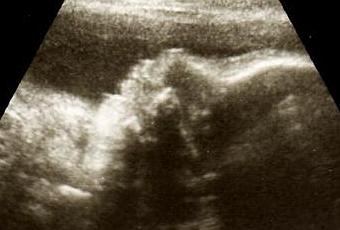

Pour moi, le début de la dernière ligne droite est caractérisée par la dernière écho, celle des 32 semaines, ultime rencontre avec ma petite fille en mode chat avant de la découvrir « en chair et en os ».

Je n’ai plus aucune appréhension, j’ai vu ma chouquette tant de fois que je sais qu’elle est parfaite et qu’elle va bien. Ce n’est donc pour moi que du plaisir d’avoir encore rendez-vous avec elle. Une fois de plus j’aurais aimé partager ça avec papa mais il travaille et la distance ne facilite pas les choses. Tant pis, une fois de plus je le tiendrai informé de l’évolution des choses par téléphone. Même s’il est encore frileux par rapport à sa paternité à ce stade de la grossesse, bien qu’ayant bien avancé vers sa petite fille depuis quelque temps, je tiens toujours absolument à le tenir au courant de tout. C’est ma façon à moi de l’impliquer, d’essayer de lui montrer le bon côté des choses, de toucher son cœur en lui parlant de bébé. Pas facile, il est retord l’animal… mais je sens quand même qu’il est loin d’être indifférent et qu’il ne s’en fout pas du tout… pas tant qu’il le dit en tous cas.

Nous voilà donc arrivés au 16 mai, date de l’échographie. Je suis enceinte de 7 mois tout juste et je commence à être bien grosse. J’ai de plus en plus de mal à me lever, à marcher, à monter les escaliers etc. Ne parlons pas des nuits d’insomnie et des envies incessantes de faire pipi.

Pour une fois la sage femme n’est pas trop en retard et elle me prend à l’heure. Après les questions d’usage, elle commence et j’aperçois la petite chieuse qui gigote ! Tout va bien mais comme j’ai la vessie à moitié pleine, je dois aller la vider pour continuer l’examen.

La petite loutre fera sa précieuse jusqu’au bout en ne voulant pas non plus nous montrer son sexe. Heureusement que j’ai eu maintes fois confirmation que c’était une fille, sinon j’aurais pu avoir quelques inquiétudes… c’est que j’ai déjà bien commencé à acheter du rose moi alors bon, vaut quand même mieux que ce soit une fifille à sa maman ! Elle se porte comme un charme et fait déjà la coquine.